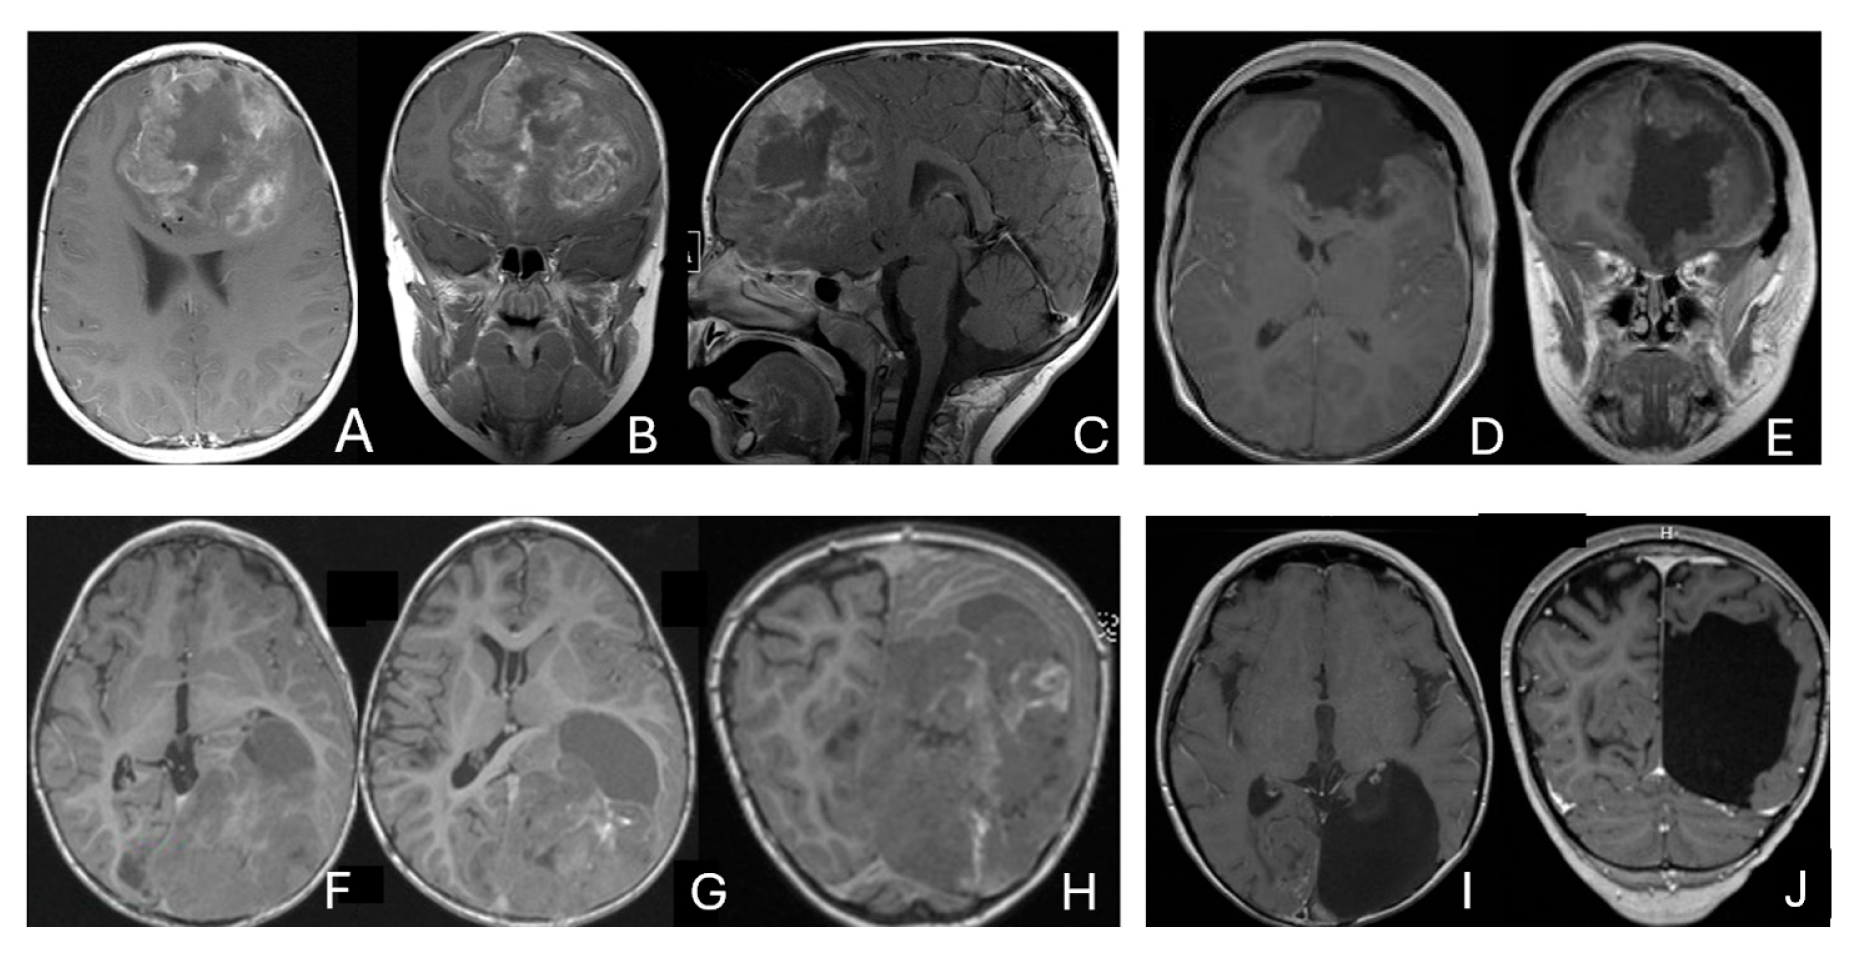

Five patients had tumors centered within the fourth ventricle; in four of these, the tumor involved the floor of the ventricle (brainstem) (Figure 7).

Figure 7.

Fourth ventricle ATRT. (A–F): MR images ((A), axial; (B), coronal; (C), sagittal) of a 21-month-old boy show a predominantly cystic fourth ventricular mass. The lesion appeared to arise from the inferior vermis, and the floor of the fourth ventricle was partially infiltrated. Postoperative images ((D), axial; (E), coronal; (F), sagittal) demonstrate gross-total resection. (G–L): MR images ((G), axial; (H), sagittal; (I), coronal) of a 3.5-year-old girl reveal a solid fourth ventricular tumor with heterogeneous enhancement. The floor of the fourth ventricle was intact, and the lesion appeared to originate from the inferior vermis. Postoperative images ((J), axial; (K), sagittal; (L), coronal) confirm gross-total resection.

In five additional patients, tumors straddled both the fourth ventricle, the lateral recess and in some further the CPA and/or the cerebellomedullary fissure (CMF), producing a dumbbell-shaped configuration (Figure 8).

Figure 8.

Fourth ventricle-lateral recess/CMFOK ATRT. (A–E): MR images ((A), axial; (B), coronal; (C), sagittal) of a 12-month-old boy show a fourth ventricular ATRT extending to the CMF through the lateral recess and with multiple peritumoral cysts. A partial invasion to the pons was noted at surgery. Postoperative images ((D), axial; (E), sagittal) demonstrate gross-total resection. Fourth ventricle-CPA ATRT. (F–J): MRI ((F): axial T2-weighted; (G): post-contrast coronal; (H): post-contrast sagittal) of a 5-month-old girl reveal a heterogeneous, dumbbell-shaped ATRT extending from the fourth ventricle into the CPA/CMF. During surgery, invasion of the lateral wall of the medulla oblongata was observed, and a subtotal resection was achieved. Post-contrast MRI ((I): axial; (J): sagittal) reveals residual enhancing tumor at the CMF.

Eight patients had lesions localized to the CPA/CMF region (Figure 9). Among them, two had concurrent bilateral lesions. In one bilateral case, the lesions were asymmetric with questionable evidence of spinal cerebrospinal fluid dissemination, whereas another patient exhibited symmetric bilateral lesions.

Figure 9.

Cerebellopontine angle (CPA) ATRT. (A–E): T2-weighted MR images ((A), axial; (B), coronal) of a 7-week-old girl show a massive ATRT centered in the right CPA/CMF. Postoperative MR images ((C), axial; (D), coronal) show a gross-total resection of a highly vascular, necrotic mass. Intraoperative photograph following tumor resection illustrates key landmarks: LR, lateral recess; V, trigeminal nerve; VII/VIII, facial and vestibulocochlear nerves; IX/X, glossopharyngeal and vagus nerves. The cranial nerves were free of tumor. ATRT appeared to originate from the lateral posterior cerebellar lobe. (F–K): MR images ((F), axial; (G), axial) of a 3.5-year-old girl show bilateral CPA tumors: a larger, partially cystic mass on the left (open arrow) and a smaller solid mass extending toward Meckel’s cave on the right (solid arrow). The left-sided tumor was resected via a retrosigmoid approach ((H), axial; (I), axial). The lesion arose from the lateral cerebellar hemisphere and extended into the CPA cistern without cranial nerve invasion. Following chemoradiotherapy, the right-sided lesion resolved ((J), axial; (K), axial).

None of the CPA ATRTs showed evidence of cranial nerve origin at the time of surgical inspection (Figure 9E).

Eleven patients were diagnosed with ATRT in the pineal region, defined in the transverse plane from the posterior third ventricle to the quadrigeminal cistern, and in the vertical plane between the corpus callosum and the superior vermis. Of these, only one patient had a lesion centered in the posterior third ventricle that appeared to arise from the pineal gland (Figure 10A–D).

Figure 10.

Pineal region ATRT. (A–D): MR ((A), axial; (B), sagittal; (C), coronal) of a 3-year-old girl show an avidly enhancing ATRT in the posterior third ventricle. Postoperative post-contrast MR ((D), sagittal) demonstrates gross-total resection. (E–I): MR images ((E), axial; (F), sagittal) of a 13-month-old boy reveals a pineal region tumor extending from the quadrigeminal cistern into the fourth ventricle with obstructive hydrocephalus. The superior vermis and fastigium (open arrow) are depressed, and the tectal plate (solid arrow) is flattened and displaced rostrally. Gross-total resection of largely necrotic ATRT was achieved via a posterior interhemispheric transtentorial approach. Postoperative MR ((G), axial; (H), sagittal) shows restoration of the tectal plate (solid arrow) and fastigium (arrowhead). The superior vermis and the ependymal lining of the fourth ventricle were not invaded. A representative brain section (I) at post mortem study from another patient with a similar presentation demonstrates intact bilateral cerebellar peduncles (arrows) and a preserved tectal plate (arrowhead). Thus, the tumor is considered to arise from the superior medullary velum.

The remaining ten tumors of the pineal region, which constitute the majority, were found to originate from the superior medullary velum (SMV) [20,21]. Characteristic neuroimaging features included posterior displacement of the superior vermis and fastigium, as well as rostral displacement of the tectum, accompanied by a mass occupying the quadrigeminal cistern and the upper fourth ventricle (Figure 10E,F). Postoperative MRI following the resection of tumors arising from the SMV demonstrated preservation of both the cerebellar vermis and the tectum (Figure 10G,H). A postmortem examination of an ATRT involving the SMV revealed a defect in the roof of the fourth ventricle, with intact superior cerebellar peduncles and tectal plate—findings that strongly suggest an origin from the SMV (Figure 10I). Among the ten patients with SMV ATRT, eight exhibited central necrosis or varying degrees of cyst formation, while one patient presented with evidence of intra-tumoral hemorrhage. All patients with ATRT in the pineal region experienced hydrocephalus, and only one patient showed MRI evidence of subarachnoid dissemination at the time of diagnosis.

The mean age at diagnosis for patients with pineal region AT/RT was 12.4 months, with most cases occurring in infancy (approximately 9 months).